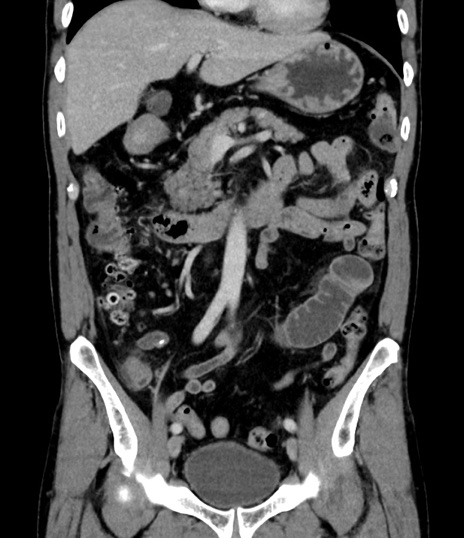

症例8(冠状断像)

【症例】 60歳代男性

【主訴】 黒色吐物

【現病歴】 4日前から嘔気自覚、2日前の朝食後にも嘔気あり、自分で手で嘔吐反射起こし嘔吐したところ血が混ざっていたため受診。

【既往歴】 5年前汎発性腹膜炎を伴う急性虫垂炎で手術、高血圧、前立腺肥大症、高脂血症

【身体所見】 腹部正中に手術癩痕あり 腹部平坦・軟圧痛なし膨満感あり

【データ】WBC 8400、CRP 4.54